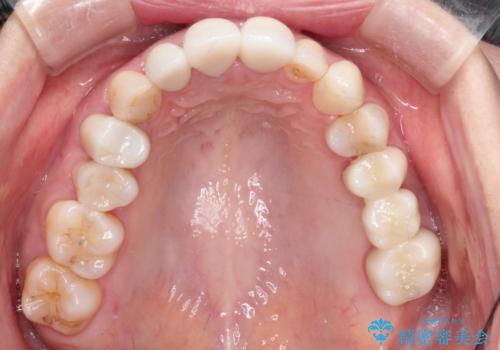

- 歯医者が怖くて悪い歯をそのままにしてしまった、悪いところを治したいとのことで来院されました。

虫歯の歯や、歯を抜いてしまったところをそのまま放置していたことにより、歯並びも悪くなっていました。

矯正をはじめ、根の治療・インプラント・セラミックによる全体治療を提案させていただき、治療をしていくこととなりました。